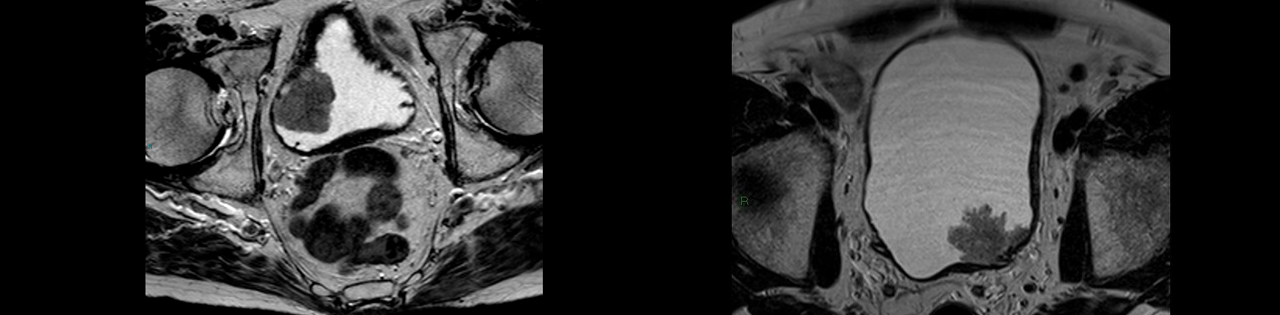

Мультипараметрическая магнитно-резонансная томография (МРТ) является основным методом предоперационного обследования с целью оценки степени инвазии (прорастания) опухолью стенки мочевого пузыря.

После первичного ТУР мочевого пузыря, при диагностике прорастания опухоли в мышечный слой по данным гистологического исследования, речь идёт о мышечно-инвазивном характере роста мочевого пузыря, который всегда имеет агрессивный характер и требует комплексное активное лечение. В настоящий момент существуют два способа радикального лечения: оперативное лечение, которое заключается в полном удалении мочевого пузыря, или комбинированная химио-лучевая терапия. Сегодня клиника Hadassah предлагает своим пациентам все возможные методы лечения инвазивного рака мочевого пузыря.